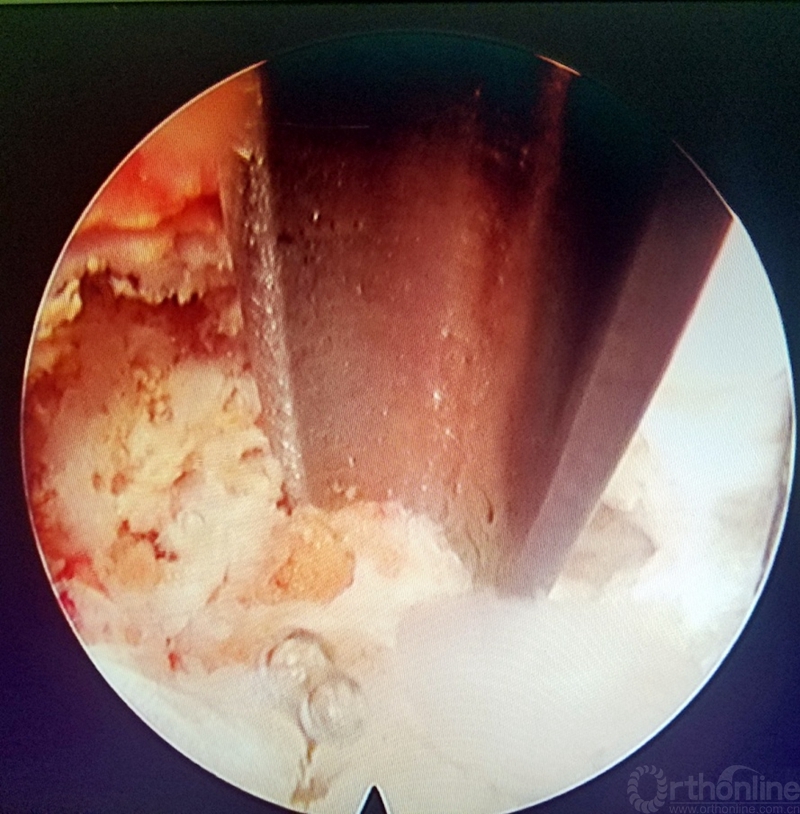

图3 椎间孔成型前

图4 直视下行关节突去除

图5 直视下行关节突去除